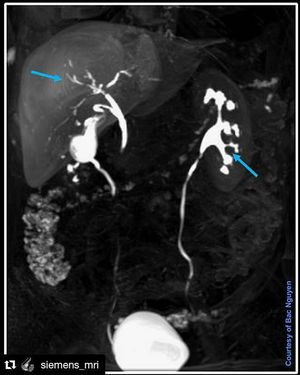

Liver Spesifict Contrast Agent Primovist/Eovist

Dual elimination approx. 50% renal system and 50% hepatobiliary system.